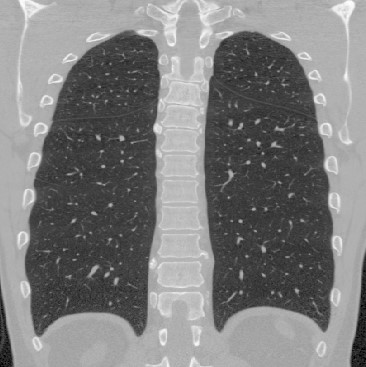

To illustrate the patterns in the radiomic biomarker information obtained across the range of disease, we examine the values from three representative individuals, from healthy, mildly abnormal (Sarc A), and very abnormal (Sarc B) CT scans. As disease becomes more apparent on the CT slices (from healthy to very abnormal) (Figure 1), the values for Moran’s increase. In contrast, the values for fractal dimension and Geary’s C decrease (Tables 3, 4, 5). An increase in Moran’s and a decrease in Geary’s C are indicative of more positive spatial autocorrelation; a decrease in fractal dimension is indicative of smoother structures. The trend in these parameters are clinically important, since we expect to see more positive spatial autocorrelation and smoother structures in CT slices as disease worsens.